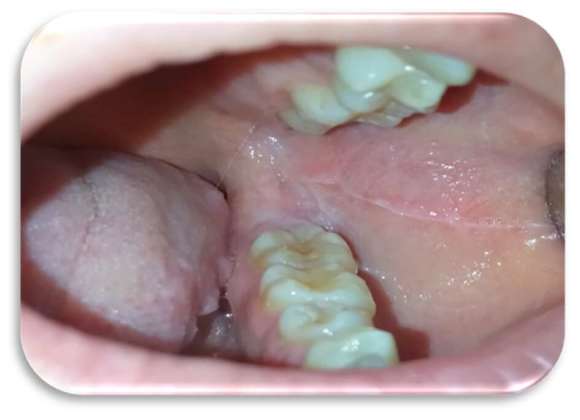

Inizialmente la paziente era stata trattata con collutorio a base di clorexidina 0,2% per circa 12 giorni senza alcun beneficio. Le lesioni si presentavano molto dolenti, erosive ed eritematose bilateralmente e simmetricamente sul ventre linguale (Figure 1 e 2) e sulla mucosa geniena, compatibili con un sospetto quadro clinico di lichen planus orale erosivo.

Sia sui margini linguali che sulle mucose geniene erano presenti, inoltre, segni di morsicatio buccarum e linea alba (Figure 3 e 4).